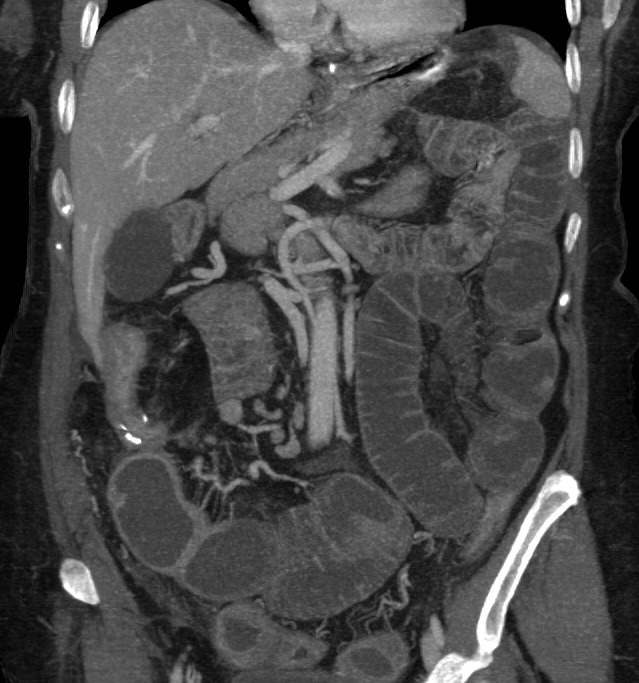

Tomografía Computarizada:

Con sensibilidad y especificidad próximas al 100%, es la técnica inicial de elección ante la sospecha de una obstruccion intestinal. Ante la sospecha firme de obstruccion intestinal, realiza un diagnóstico más preciso, aporta más información adicional y evita retrasos en el diagnóstico.

Hallazgos:

- Distensión proximal a la obstrucción mayor de 3,5 cm en el intestino delgado y mayor de 5 cm en el colon con colapso de asas distales junto con la identificación, siempre que sea posible, de la zona del cambio de calibre (zona de transición), lo que nos permite realizar con mayor seguridad el diagnóstico.

- Si se observan asas dilatadas, independientemente del grado, si no hay colapso de asas distales, el diagnóstico más probable es un íleo paralítico.

- Nivel de la obstrucción: determinado por la zona de cambio de calibre.

- En caso de obstrucción de un asa de colon existirá dilatación del colon proximal. Si la válvula es incompetente existirá también, además, dilatación de intestino delgado.

- Giro o remolino de vasos mesentérico pueden sugerir una volvulación.